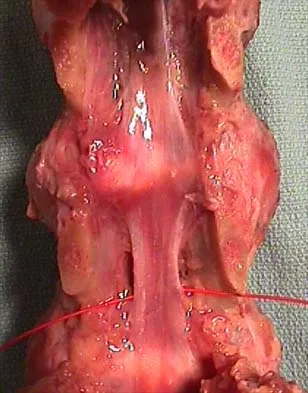

A 24-year-old man sustains the injury shown in Figures 19a through 19e in a paragliding accident. He is neurologically intact. He also sustained fractures of his left femur and right distal radius. Which of the following represents the best option for management of the spinal injury?